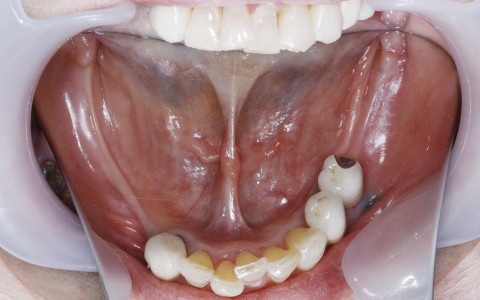

- 主訴

- 義歯を入れていて歯を失くしてきたのでインプラントをしたい

- 治療内容

- インプラント

- 治療期間

- 5ヶ月

- 治療費用

- 3,454,000円(税込)

- リスク・副作用

- 手術を伴う。チタンに対して金属アレルギーの方は適応ではない。骨粗鬆症の治療薬を使用されている方は骨壊死がおこる可能性がある。